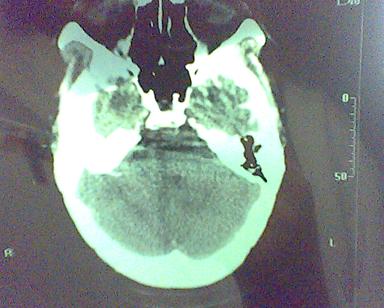

男 31岁 短暂性四肢抽搐 呼叫不应  头胀痛4个多月 无发热 4年前遭棒击头部,当时未到医院检查。余无特殊。病人特穷,未作增强。

这是一个边缘清晰的等密度的囊性占位.密度比较均匀,周围无水肿,我顷向于脑脓肿的可能性大.

右侧乳突蜂房消失,右侧颞叶区囊性占位,水肿不明显,考虑表皮样囊肿或耳源性脑脓肿,+c!。